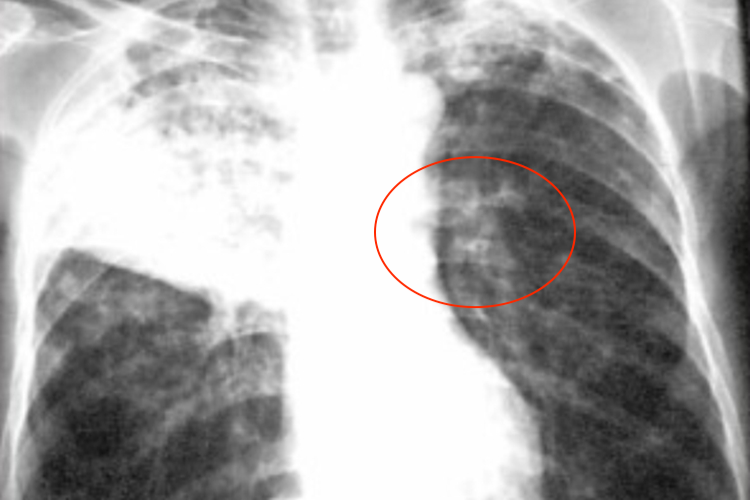

干酪性肺炎:呈大叶性密度均匀磨玻璃状阴影,逐渐出现溶解区,呈虫蚀样空洞,可出现播散病灶。有时也可呈小叶斑片播散病灶,多发生在双肺中下部。